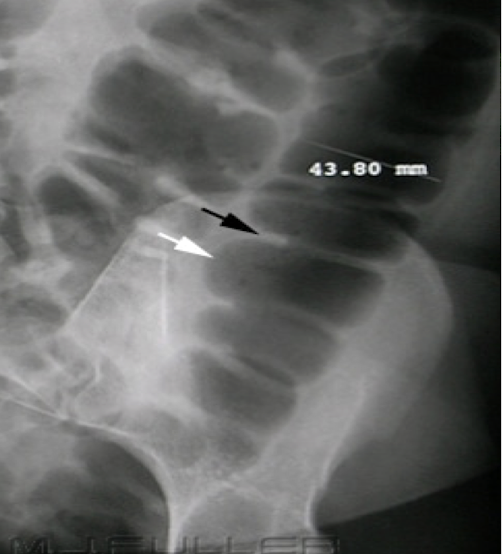

Cecal volvulus

section of twisted bowel causing obstruction and strangulation

Abdominal Radiograph

Sigmoid volvulus

“coffee bean” sign

section of twisted bowel causing obstruction and strangulation

Abdominal Radiograph